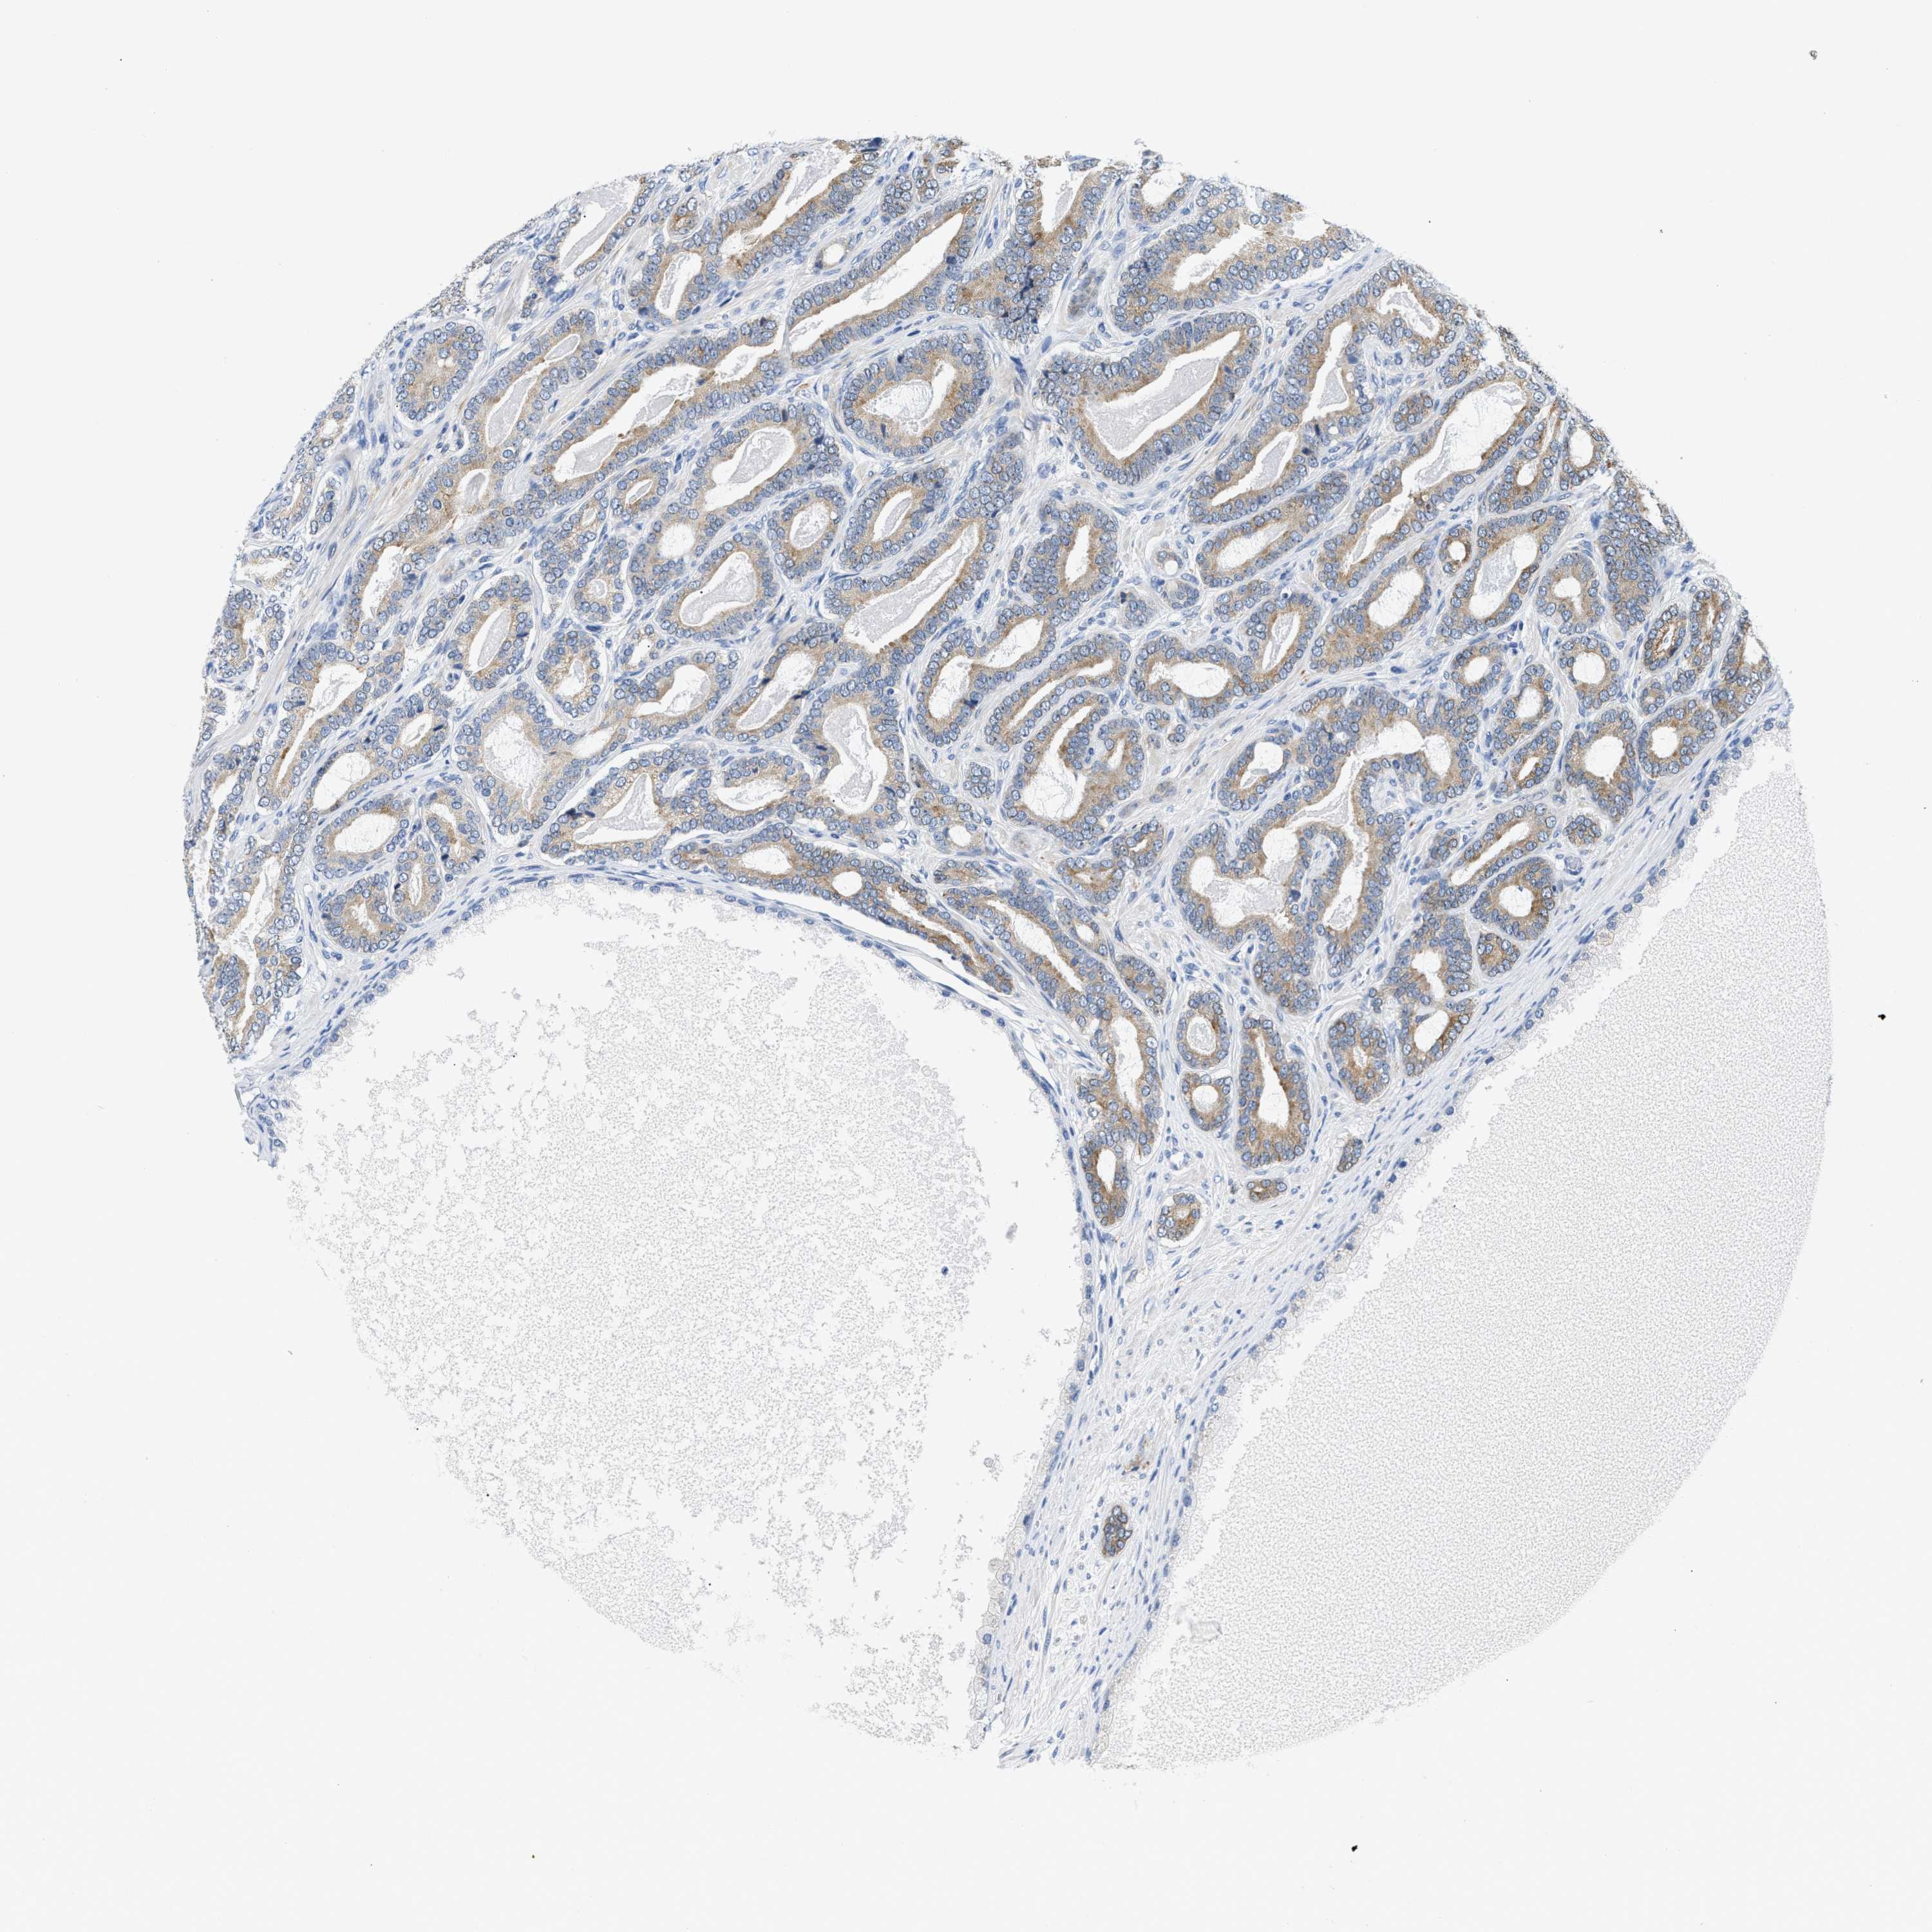

PROSTATE CANCER - Protein expressioni

A mouse-over function shows sample information and annotation data. Click on an image to view it in a full screen mode. Samples can be filtered based on level of antibody staining by selecting one or several of the following categories: high, medium, low and not detected. The assay and annotation is described here.

Note that samples used for immunohistochemistry by the Human Protein Atlas do not correspond to samples in the TCGA dataset.

Antibody stainingi

Antibody staining in the annotated cell types in the current human tissue is reported as not detected, low, medium, or high, based on conventional immunohistochemistry profiling in selected tissues. This score is based on the combination of the staining intensity and fraction of stained cells.

Each image is clickable and will lead to virtual microscopy that enables deeper exploration of all samples and also displays staining intensity scores, fraction scores and subcellular localization as well as patient and tissue information for each sample.

Antibody HPA048761

Antibody HPA058627

Antibody CAB020709

Staining

High

Medium

Low

Not detected

Intensity

Strong

Moderate

Weak

Negative

Quantity

>75%

75%-25%

<25%

None

Location

Nuclear

Cytoplasmic/membranous

Cytoplasmic/membranous,nuclear

Adenocarcinoma, High grade

Adenocarcinoma, NOS

Adenocarcinoma, Low grade